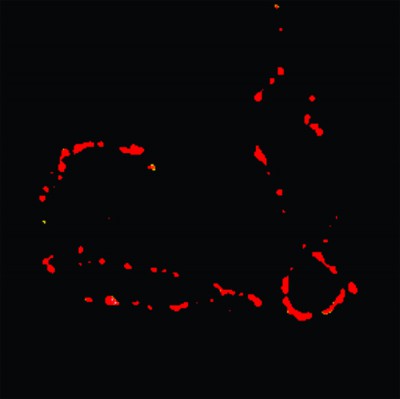

Imagen que muestra la fluorescencia del sensor de acidez en la célula.

El laboratorio, que estaba encabezado por la doctora Elizabeth Jares-Erijman hasta su muerte en septiembre de 2011 a los 50 años, está desarrollando particularmente un sensor de acidez derivado de Quantum Dots (material semiconductor fluorescente) para su aplicación en microscopías de fluorescencia.

Como modelo para los experimentos in vivo, los científicos están aplicando los nanosensores en una línea celular de ovario de hámster chino. “El objetivo es medir los niveles de acidez en el interior y exterior de las células”, explicó la doctora Carla Spagnuolo, investigadora de CONICET e integrante de ese grupo. “Se ha establecido que el nivel de acidez en esos medios está influenciado por diversos procesos fisiológicos y patológicos, por ejemplo el desarrollo de diversos tumores, fibrosis quística y asma.”

Créditos: Gentileza de la doctora Carla Spagnuolo